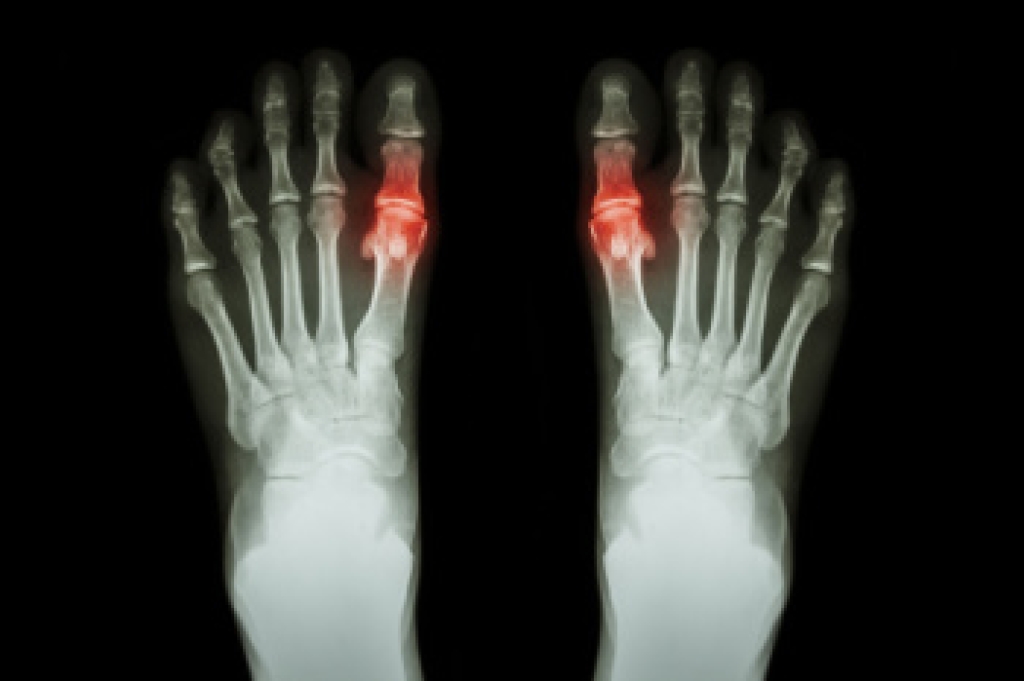

Gout is a form of arthritis marked by sudden, intense joint pain, often starting with the big toe. This condition occurs due to the accumulation of uric acid crystals in the joint, causing inflammation. Symptoms typically include severe, throbbing pain that may begin unexpectedly, often at night. The affected joint becomes swollen, red, and warm to the touch, and even light pressure from clothing or bedding can be excruciating. Warning signs of an impending gout attack include persistent joint discomfort, frequent episodes of pain, or swelling without a clear cause. If you have any of the above symptoms, it is suggested that you consult a podiatrist who can help to manage this condition.

Gout can easily be identified by redness and inflammation of the big toe and the surrounding areas of the foot. Other symptoms include extreme fatigue, joint pain, and running high fevers. Sometimes corticosteroid drugs can be prescribed to treat gout, but the best way to combat this disease is to get more exercise and eat a better diet.